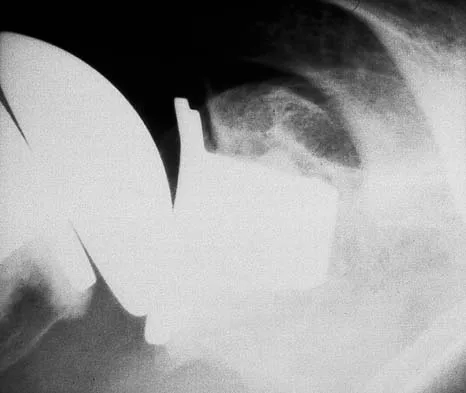

After closed reduction of the dislocation shown in Figure 42, it is essential to avoid placing the upper extremity in what position for the first 4 to 6 weeks?

Explanation